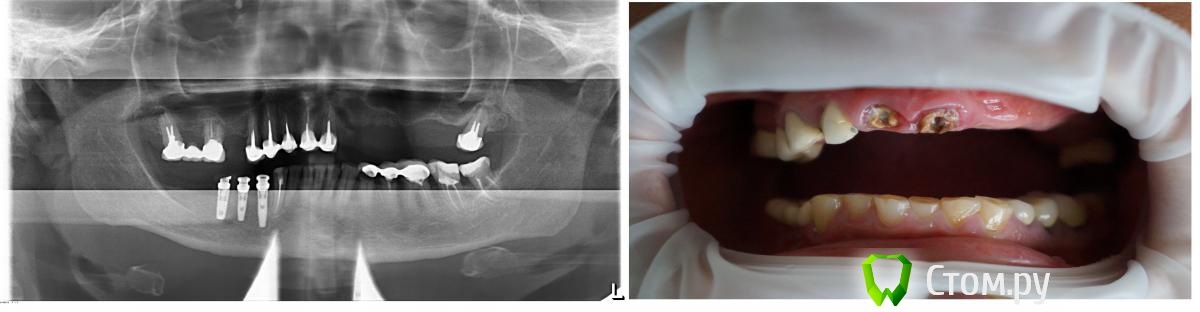

Брат 2 Опубликовано 15 ноября, 2013 Поделиться Опубликовано 15 ноября, 2013 Уважаемые коллеги планирую очередное тотальное вмешательство. Ссылка на комментарий

Брат 2 Опубликовано 15 ноября, 2013 Автор Поделиться Опубликовано 15 ноября, 2013 На в/ч планирую оставить 1.3 1.4 1.6 для мостовидного протеза, импл в позицию 1.2,второй сегмент синус+ 4 импл в позиции 2.3 2.4 2.5 2.6, мост протез 1.2-2.6,На н/ч установил 3 импл с врем. Сходятся ли наши мнения? )) Ссылка на комментарий

viruzzz Опубликовано 15 ноября, 2013 Поделиться Опубликовано 15 ноября, 2013 а с низом что дальше? выраженная стираемость зубов, уменьшение межальвеолярной высоты...я бы предпочел имплантацию в позициях 12-22-24-26если 12 действительно надо удалять... Ссылка на комментарий

Брат 2 Опубликовано 15 ноября, 2013 Автор Поделиться Опубликовано 15 ноября, 2013 Низ полностью после верха. 2.2 отсутствие объёма кости. На счёт удаления 1.2 1.1 2.1 пока не решил, поэтому и создал тему. Арки по нисходящей от центральных к жевательным, если удалю ещё выше подскочат и зенит 1.2 будет намного выше 1.3 Хотелось бы обойтись без удалений. Длина резцов останется приемлемой. Мне кажется переход между 2.1 и 2.2 будет меньше заметен. Губа при улыбке в области 2 сегмента гораздо ниже. В понедельник будет КТ. Станет чуть яснее. Ссылка на комментарий

Брат 2 Опубликовано 16 ноября, 2013 Автор Поделиться Опубликовано 16 ноября, 2013 Тогда уже 23, 25 и 26, чтобы сохранить адекватное расстояние между платформами. А лучше сделать шаблон и отправить с ним на КТА что скажете по поводу удаления резцов? Ссылка на комментарий

Pavluha Опубликовано 23 ноября, 2013 Поделиться Опубликовано 23 ноября, 2013 Я бы не стал устанавливать имплантаты в данной ситуации.Прежде всего - жесткая каппа на верхнюю челюсть с разобщением 2-4 мм - 6 месяцев минимум. Закрепление высоты на временных ч/с верх и низ + временные коронки на оставшиеся зубы. Санация полости рта. Установка имплантатов. Протезирование. Ссылка на комментарий